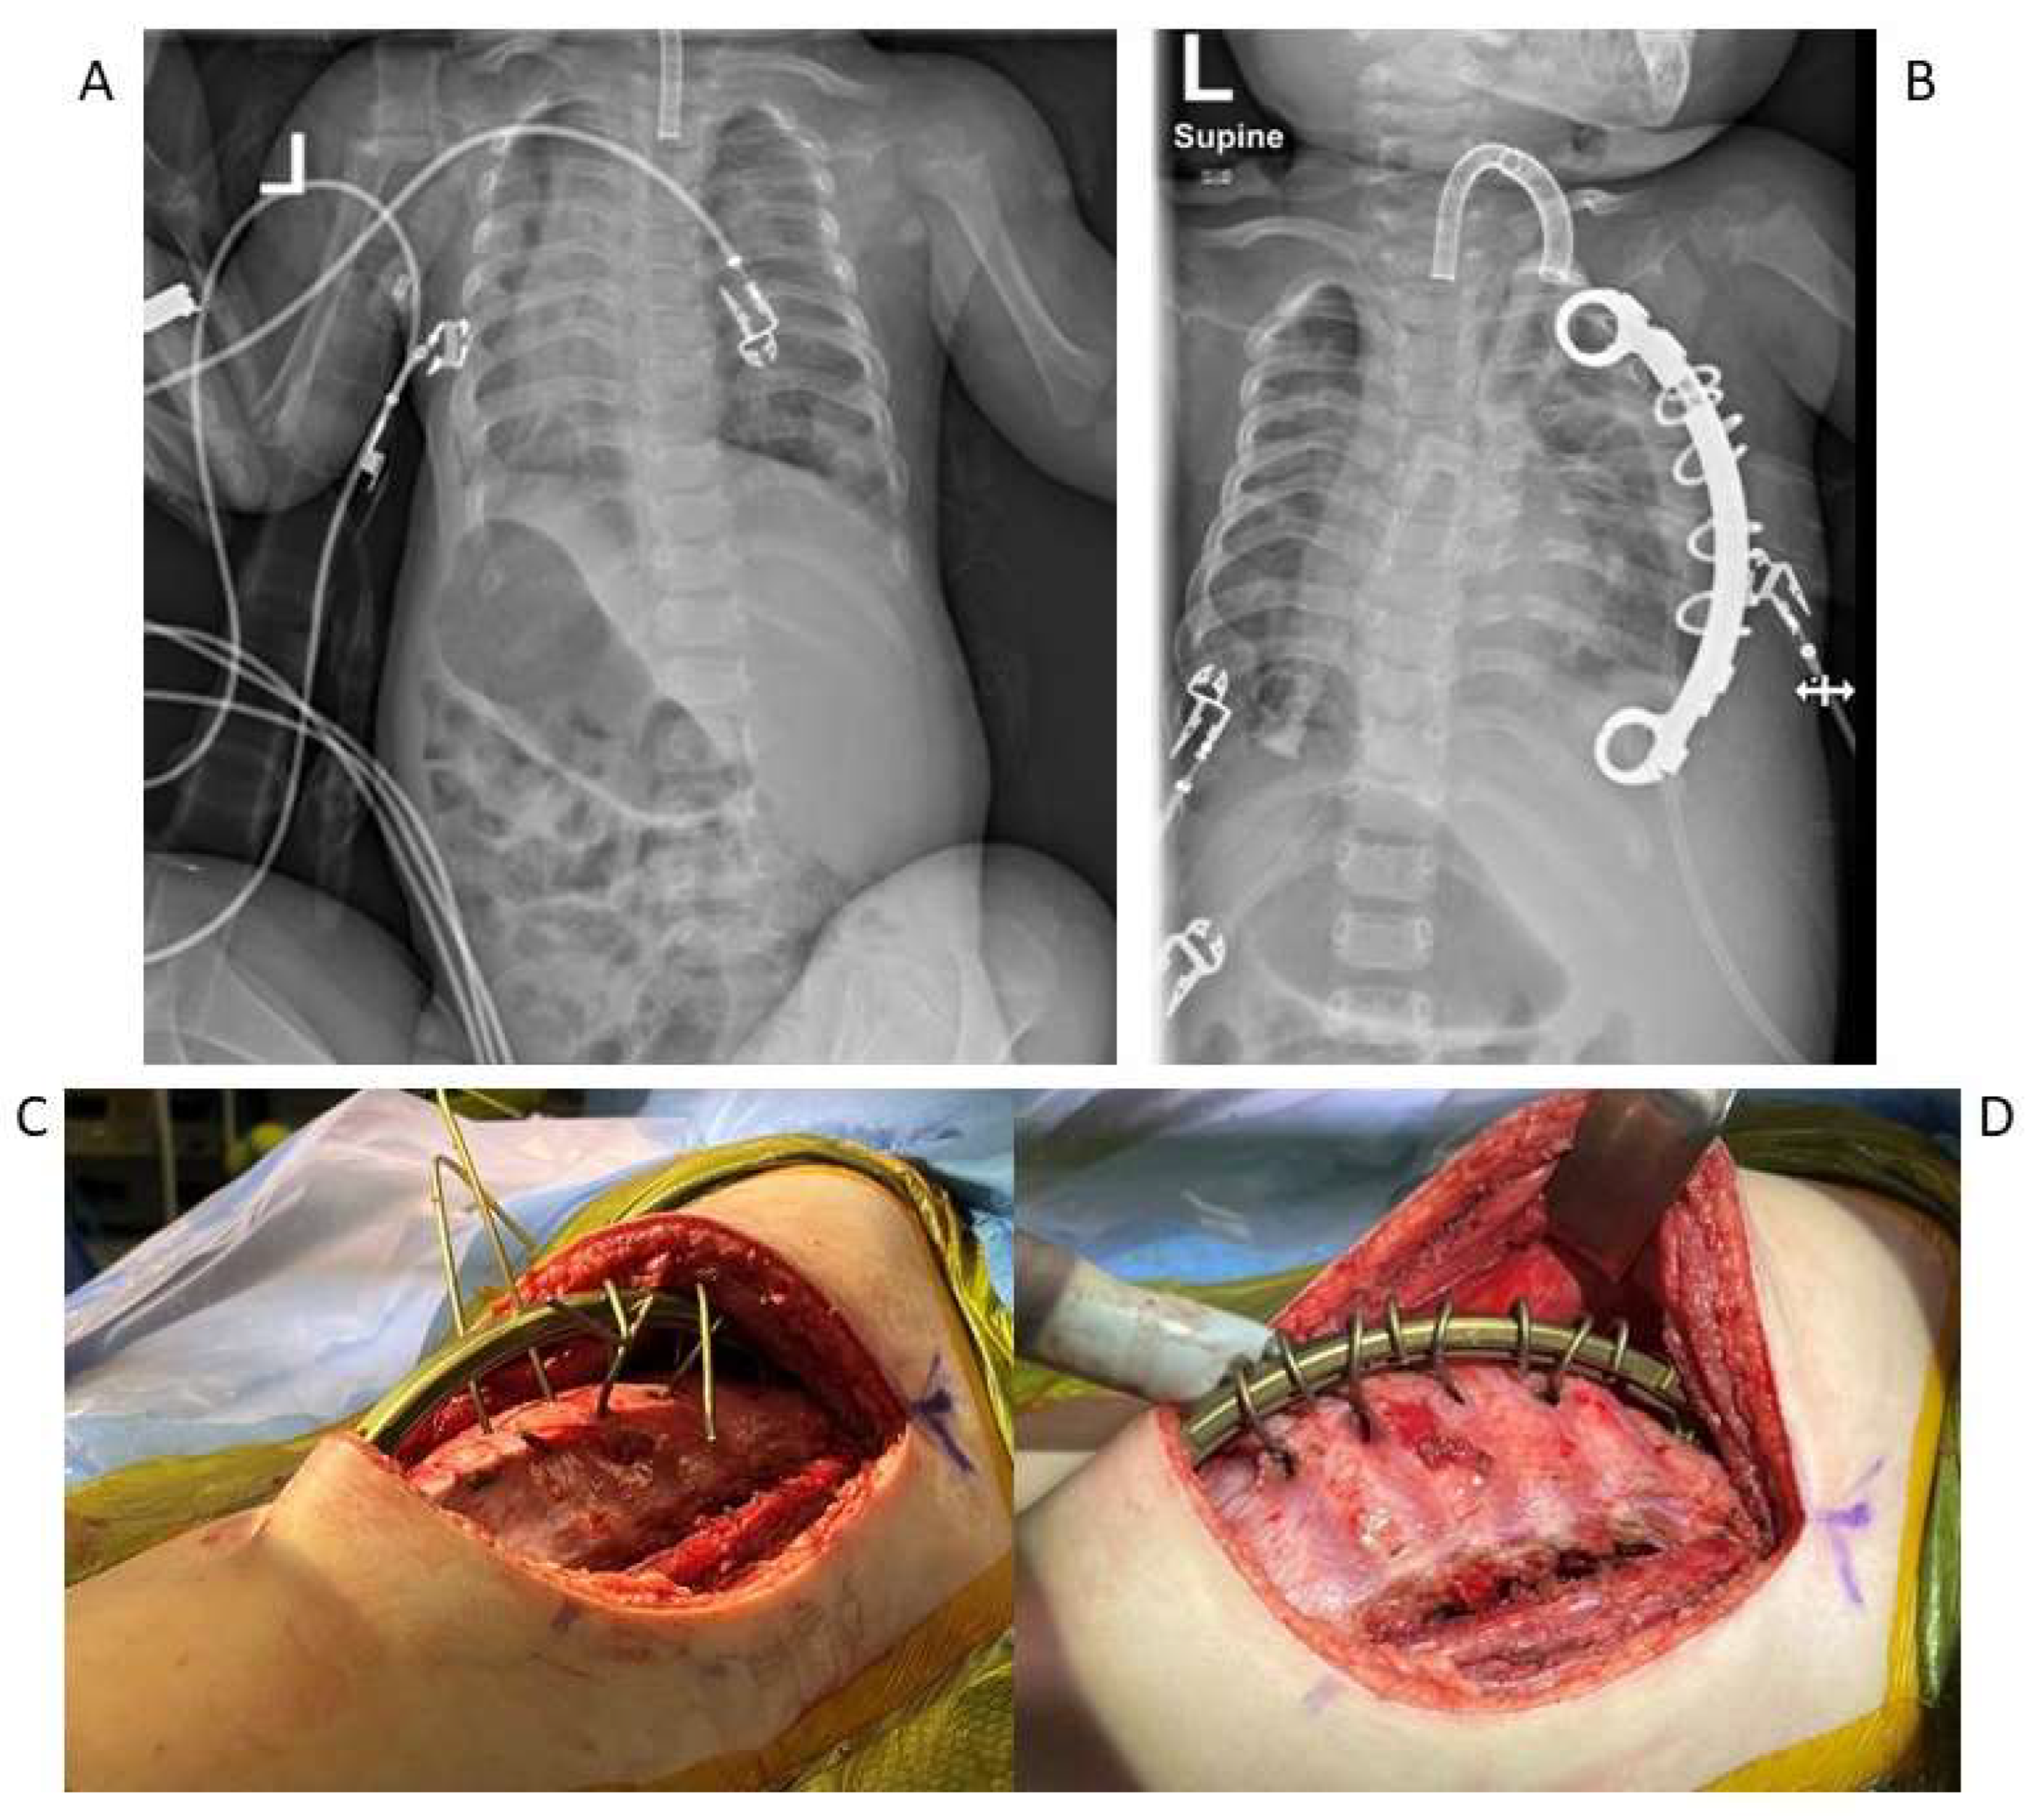

- Campbell, R.M.; Smith, M.D.; Mayes, T.C.; Mangos, J.A.; Willey-Courand, D.B.; Kose, N. The effect of opening wedge thoracostomy on thoracic insufficiency syndrome. J. Bone Joint. Surg. Am. 2004, 86, 1659–1674. [Google Scholar] [CrossRef]

- Campbell, R.M.; Vocke, A.K. Growth of the thoracic spine in congenital scoliosis after expansion thoracoplasty. J. Bone Joint Surg. Am. 2003, 85, 409–420. [Google Scholar] [CrossRef] [PubMed]

- Emans, J.B.; Caubet, J.F.; Ordonez, C.L.; Lee, E.Y.; Ciarlo, M. The treatment of spine and chest wall deformities with fused ribs by expansion thoracostomy and insertion of vertical expandable prosthetic titanium rib: Growth of thoracic spine and improvement of lung volumes. Spine 2005, 30, S58–S68. [Google Scholar] [CrossRef]